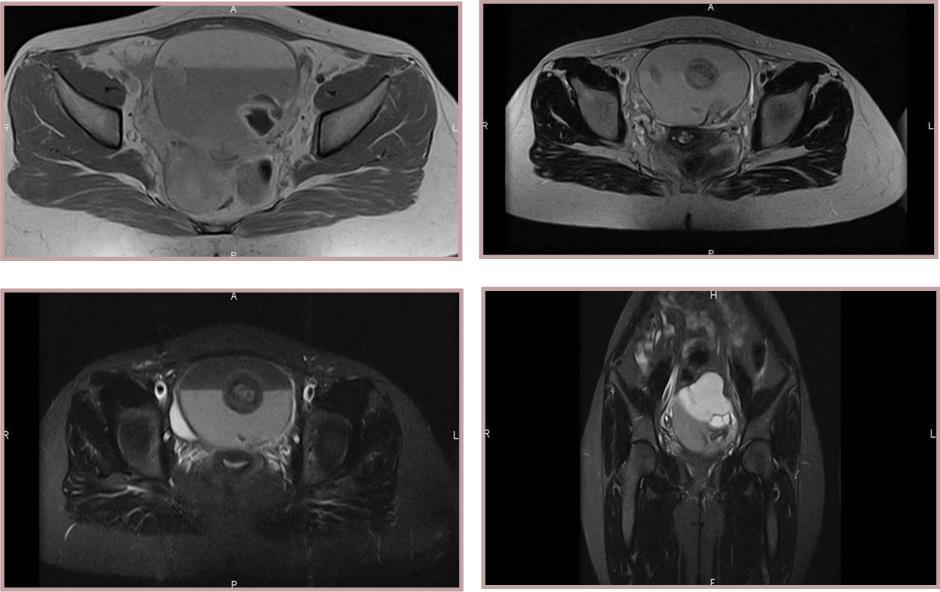

Figure 1(a,b,c,d ).Two lesions within cystic component measuring 6 x 7 x 8 cm. MRI reveals a large and well-defined encapsulated tumour. Two solid components with an intermediate signal in T2 and T1 with a moderate contrast enhancement on T1 weighted.

A transabdominal or transvaginal ultrasound reveals a large hyperechoic mass with posterior shadow-cone because of the sebaceous and hair materials or a hypoechoic cyst if it contains only sebaceous material liquid. The bones and teeth appear hyperechoic 8. MCT are sometimes difficult to distinguish on ultrasound from hemorrhagic cysts, mucinous cystic neoplasm and endometriomas 9. In these cases, the magnetic resonance imaging (MRI) plays an important role in diagnosis. Cystic teratoma appears as a large pelvic monocular cyst with a solid nodule named Rokitansky protuberance attached to a thin wall and protrudes in the cyst lumen. Figure 2 Standard T1 weighted images with fat saturated T1 weighted images establish the diagnosis when the fat removed and the fluid-fat levels is also seen. The sebaceous component of cystic teratoma is hyper-intense on T1-weighted images Figure 4. Findings of calcifications are variable and difficult to detect. Figure 3 However, 7% of MCT don't contain any fat or calcifications 10. IV contrast gives a small nodule and wall cyst enhancement. The relationship between the teratoma and other anatomic pelvic structures can be well evaluated 11.